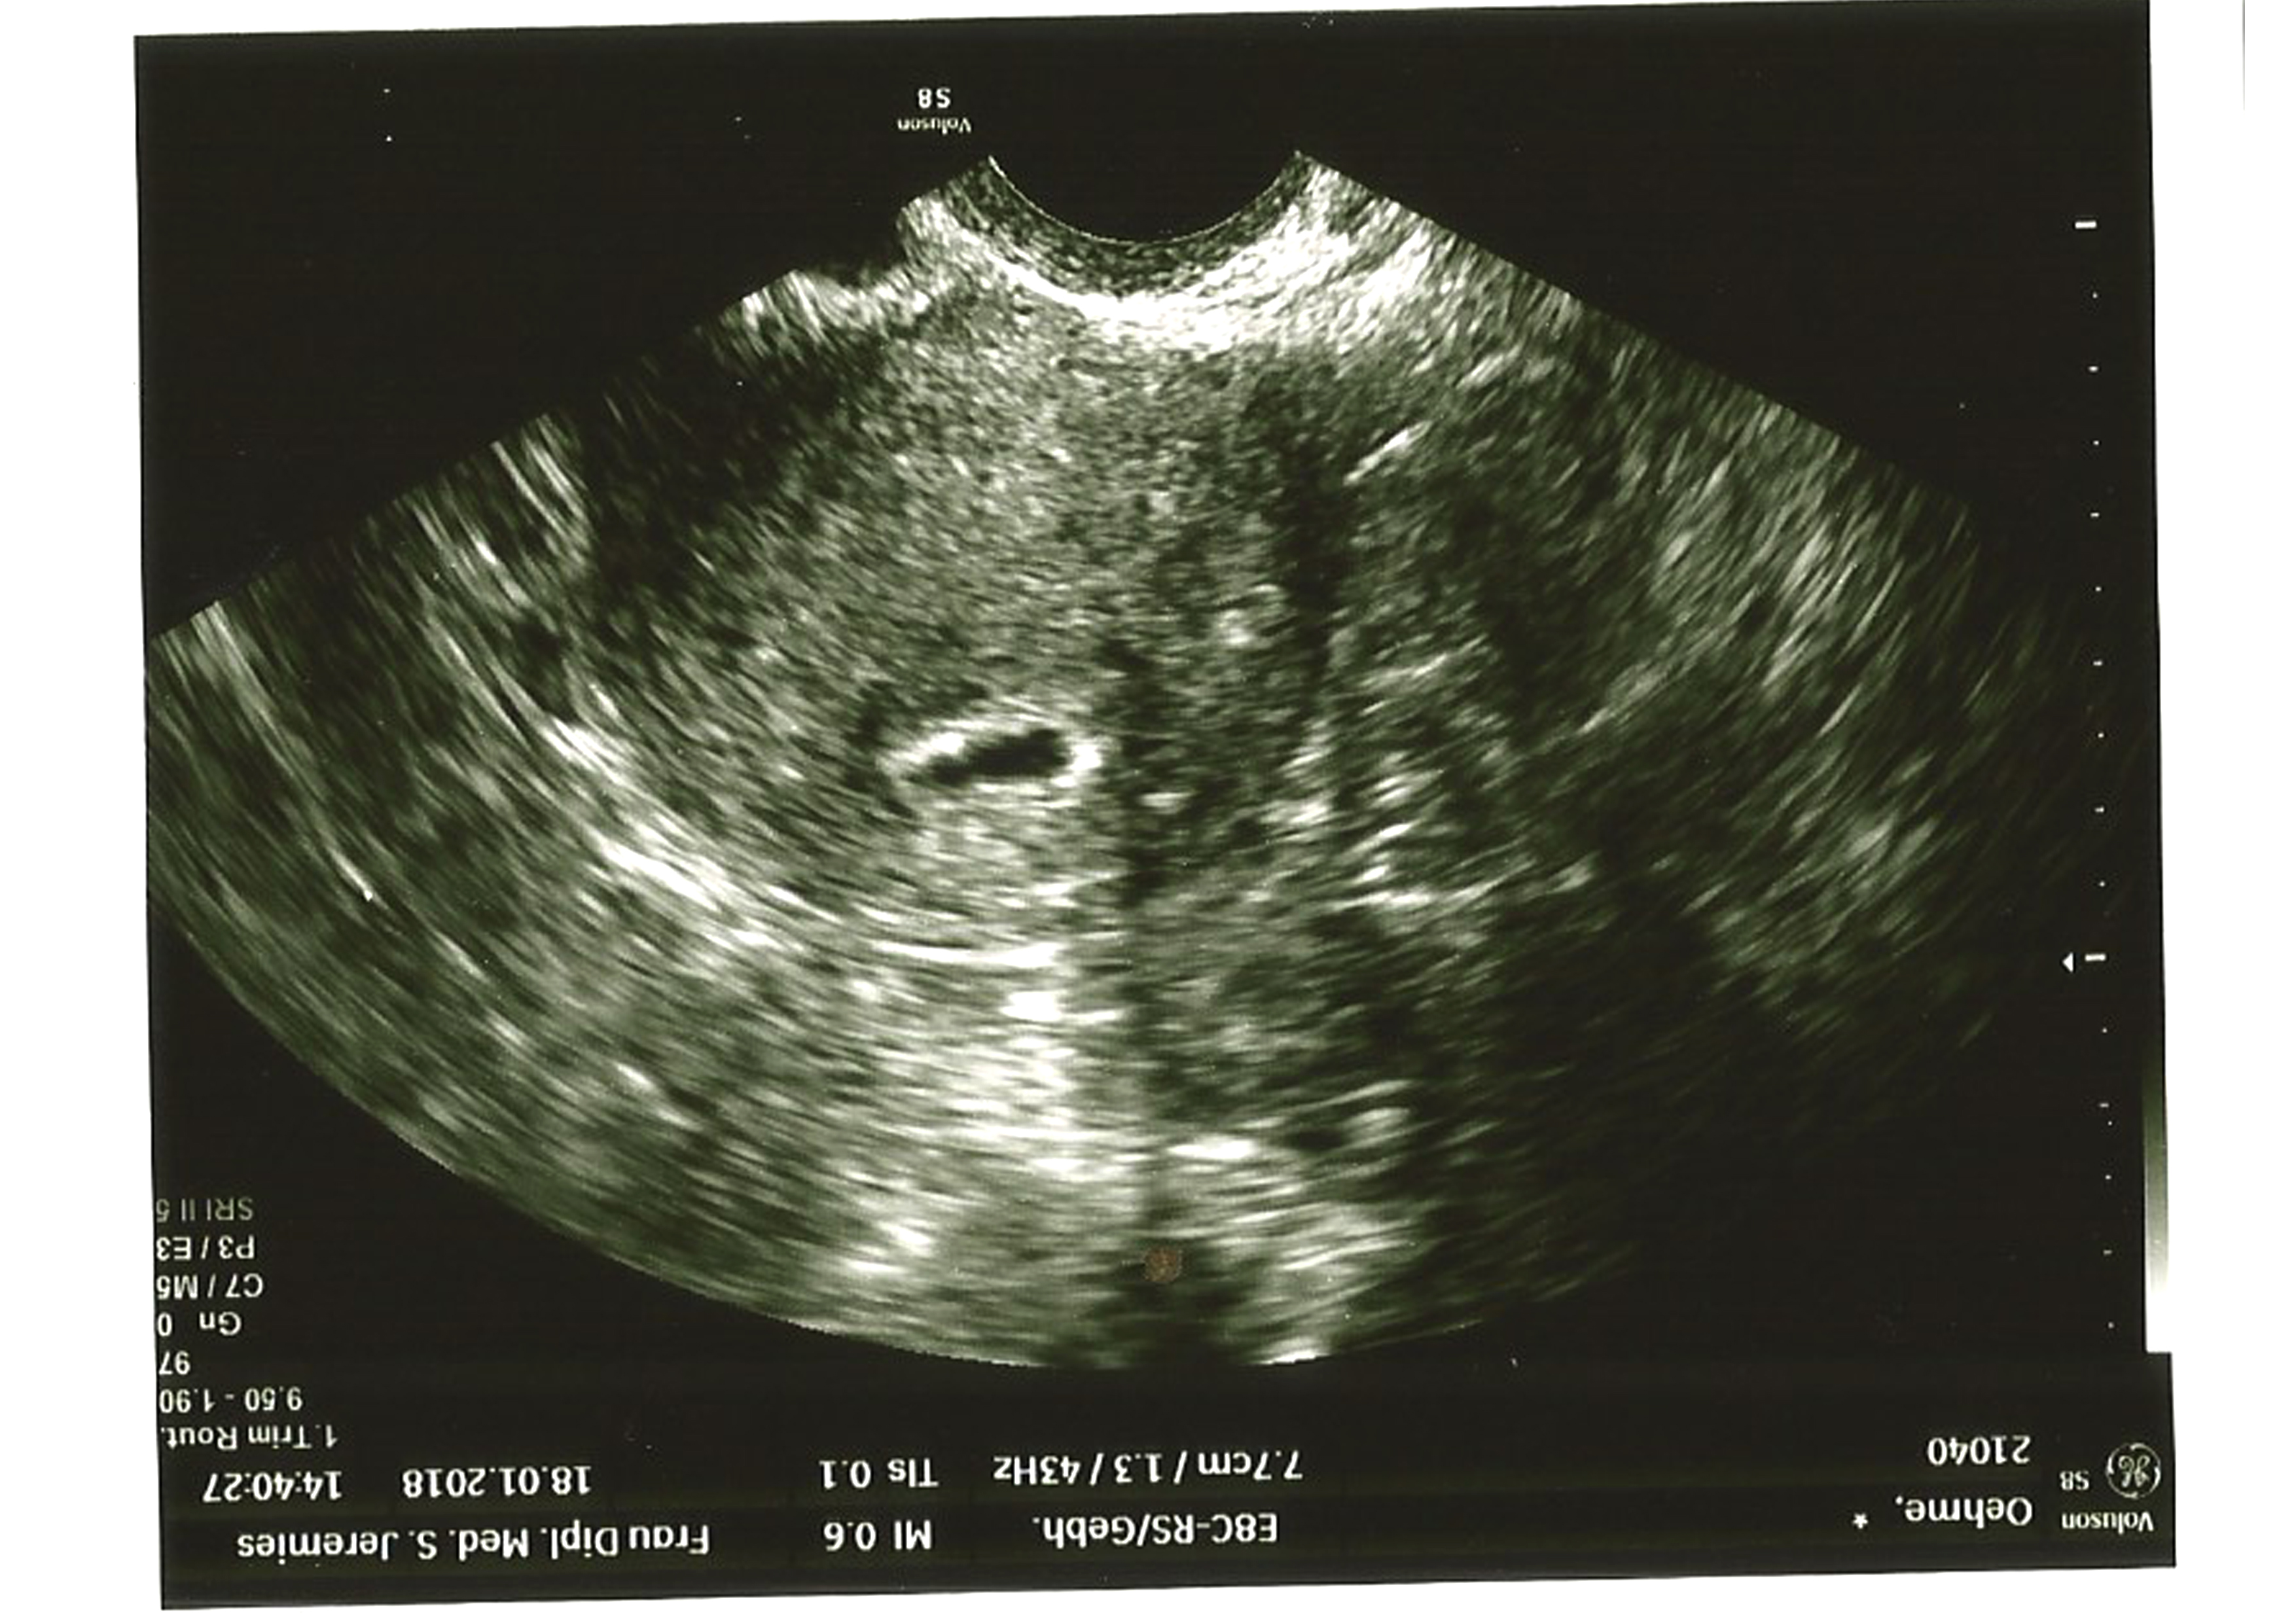

6 Ultraschall in der 6 SSW Wenn du in der 6 Schwangerschaftswoche deinen ersten UltraschallTermin hast, wirst du wahrscheinlich die Fruchthöhle und den Dottersack sehen können Hier kann man auch feststellen, ob das Baby in der Gebärmutter eingenistet ist und der Arzt kann die Schwangerschaft bestätigen. Ultraschallbild (6 SSW) 5 November 19 um 1103 Letzte Antwort 10 November 19 um 1117 Guten Morgen, am Samstag habe ich durch einen Test erfahren, dass ich in der 3 Woche schwanger bin War gerade beim Arzt und wir haben einen Ultraschall gemacht. St nikolaus bilder gif;.

5 SSW Ultraschall Das ist zu sehen Schwarzsehen war noch nie so schön Auf dem Ultraschall bestätigt in der 5 SSW ein kleiner schwarzer Punkt, dass Sie schwanger sind – das ist die Fruchtwasserhöhle, die jetzt circa einen Zentimeter groß ist Der Ultraschall bedingt, dass sie sich als schwarze Blase auf dem Bild abzeichnet. SSW SSW Wichtige Daten zu Deiner 31 ;. Alles andere als leicht Man sieht das Baby live im Ultraschall und kann auch Kopf und Hände identifizieren, aber auf so manchem Bild wird es schwierig Wir zeigen dir, wie Herz, Nabelschnur etc in unterschiedlichen Schwangerschaftswochen auf dem Ultraschallbild aussehen Dazu gibt es noch ein paar niedliche 3DUltraschallAufnahmen, bei denen nichts erklärt werden muss.

1 Dein Körper in der 6 SSW In der 6 Schwangerschaftswoche (50 bis 56) beginnt die Gebärmutter in deinem Körper zu wachsen Nun können Ärzte und Hebamme diese von Außen ertasten und auch der Gebärmutterhals fühlt sich verändert an Während er vorher weich und beweglich war, ist er nun fest und weniger beweglich, was als „Pschyrembelsch StockTuchZeichen“ bezeichnet wird. Ultraschallbild aus der 27 SSW Dopplerultraschall (Blutfluss in den Blutgefäßen) 3DUltraschallbild aus der 27 Woche In der 27 SSW macht das Gehirn des kleinen Bauchbewohners große Sprünge Bisher war dessen Oberfläche glatt. Meist wird in der 6 SSW noch kein Ultraschallbild gemacht, sondern der Frauenarzt stellt in der Erstuntersuchung fest, ob alles einwandfrei läuft, und tastet Deinen Bauch ab Du bekommst einen Mutterpass, in dem alle wichtigen Daten notiert werden und den Du immer mitführen solltest Üblich sind 3 große Hauptuntersuchungen mit Ultraschall.